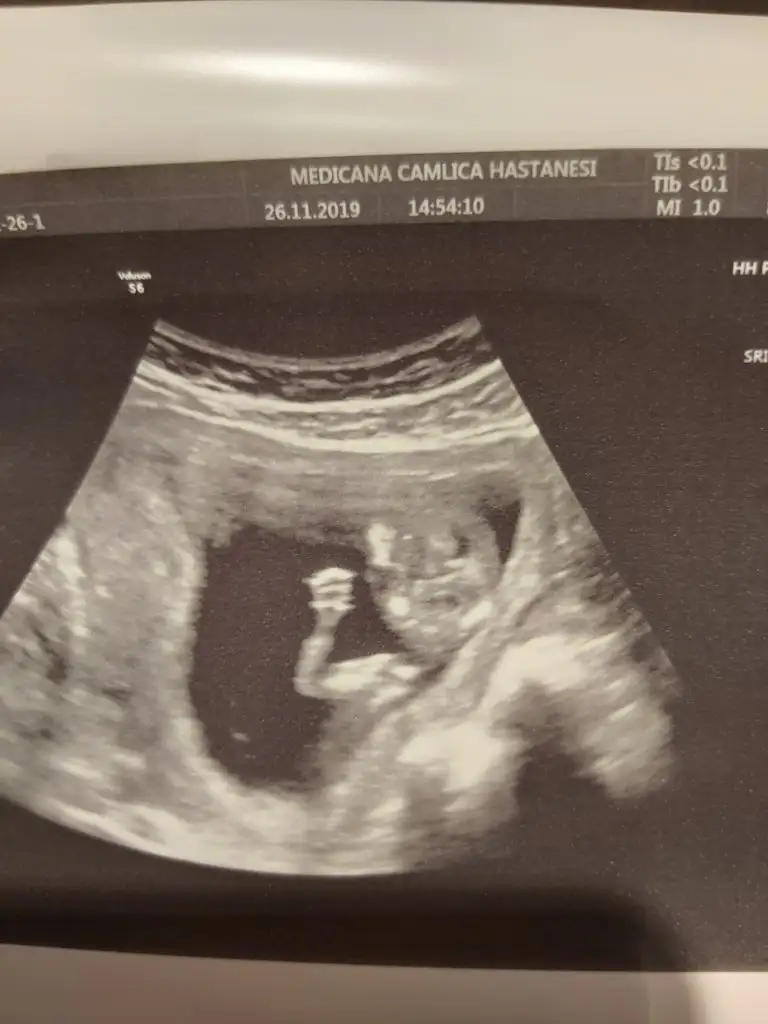

Ama o nub çıkıntısı değil ayak sankiBunu ben bile anladım bu erkek![]()

Buna da bakarmısınız 11+5 arkadaşın

13. Haftalık 11 ve 12. Haftalıkken doktora gitmedik kontrolümüz 13. Haftaya denk geldi o yüzden bu başka da var ama net değil ki atayım ben yine deerkek gibi başka usg var kaç haftalık